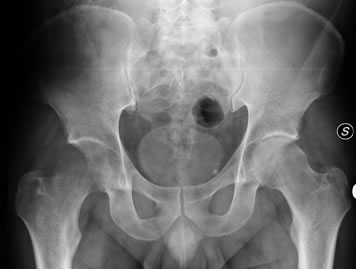

Alla radiografia compare un’area di marcata osteorarefazione a carico della testa del femore di destra. Questo segno, peraltro, sfumato, è pero' tardivo. Nelle fasi iniziali pur essendoci un'intensa sintomatologia dolorosa, con impotenza funzionale, la radiografia risulta quasi sempre negativa. Occore pertanto in questi casi procedere ad indagini diagnostiche di II livello, nello specifico la Risonanza Magnetica.

Fig 1 Edema transitorio della testa del femore destro alla radiografiaFig 1 Edema transitorio della testa del femore destro alla radiografia